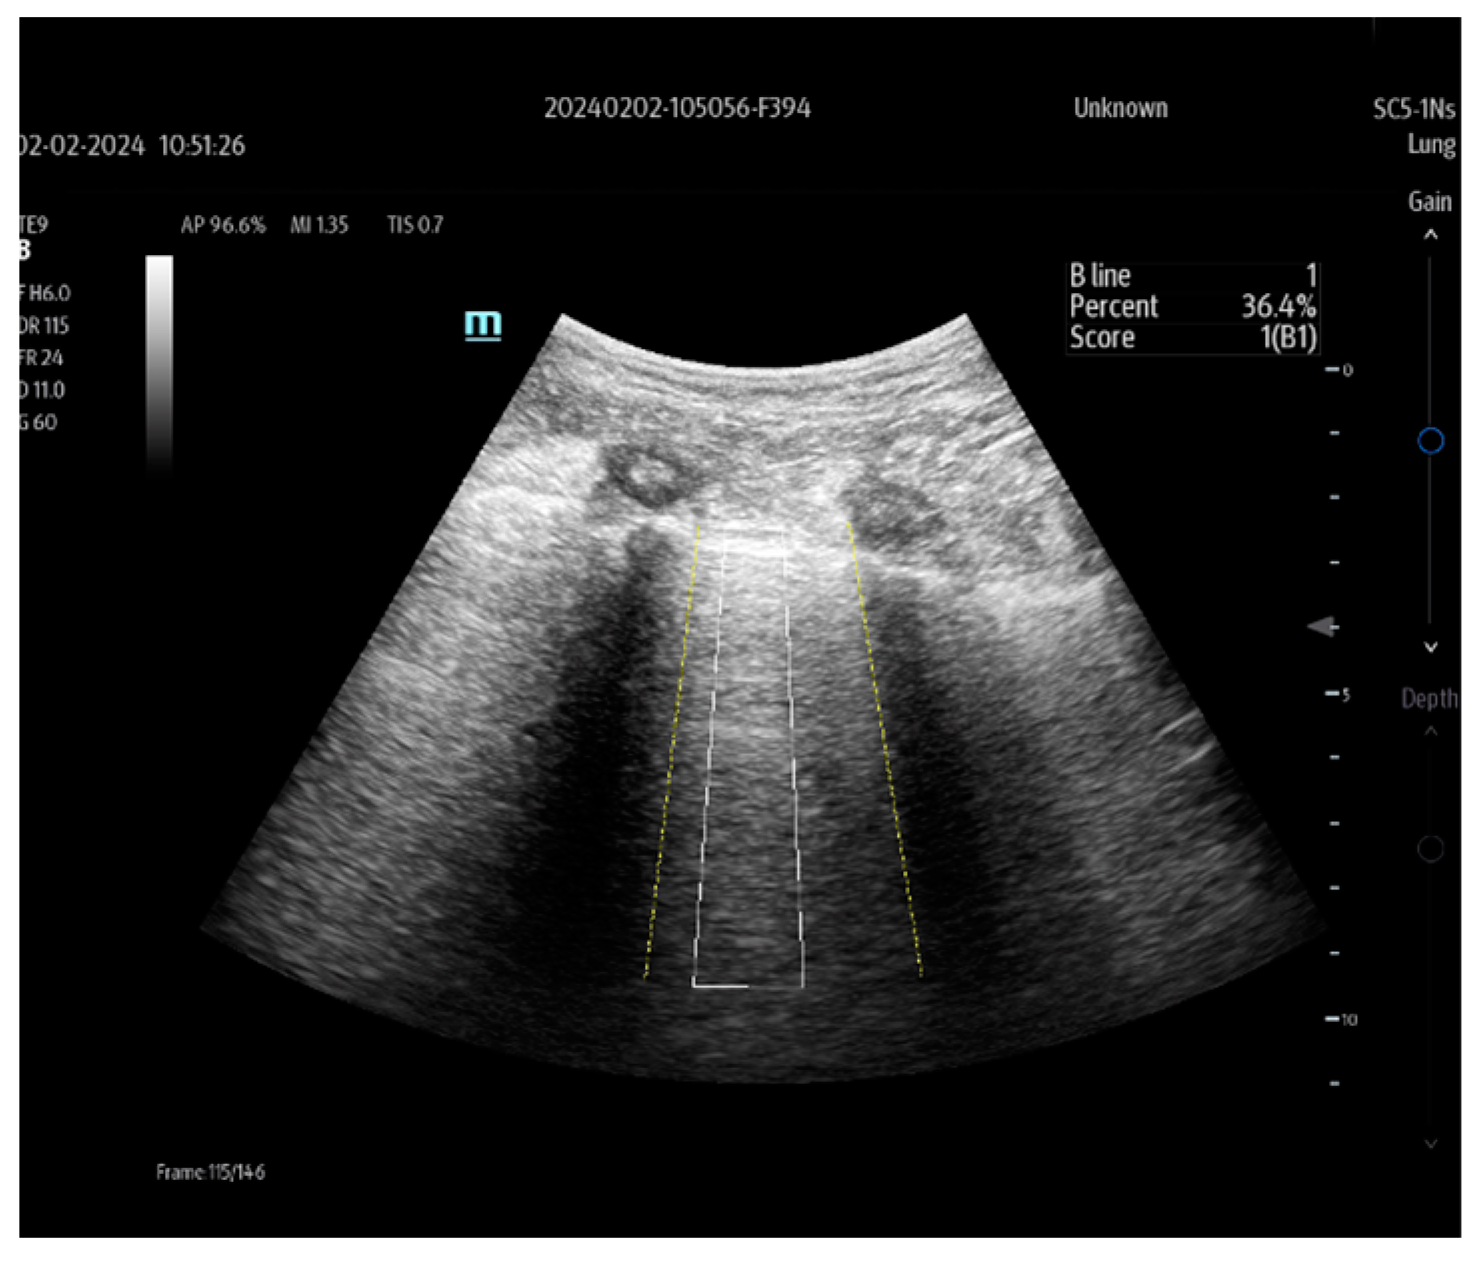

| Smart B-line | Mindray | automatic identification of the artifacts | Lung examination |

| Butterfly ScanLab | Butterfly Network | ||

| Auto B-line | GE | ||